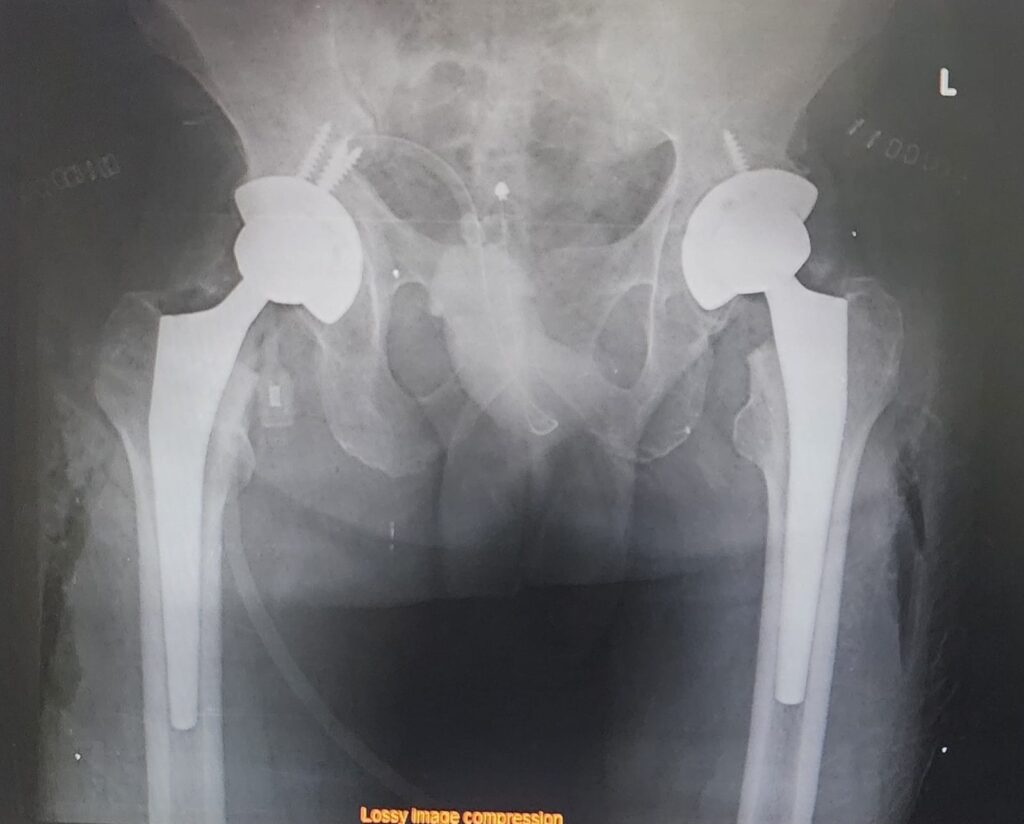

🩻 After Surgery

The post-operative X-rays show:

- Perfectly aligned prosthetic hips

- Restoration of joint height and symmetry

- Stable implants positioned accurately in both acetabula and femoral shafts